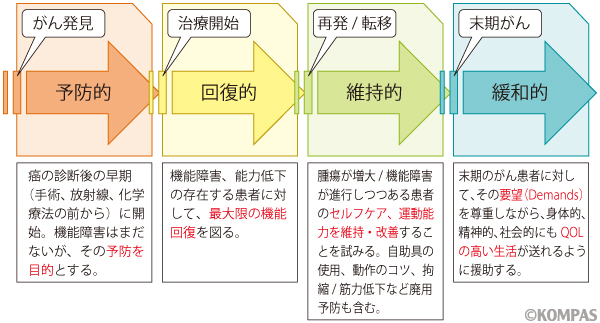

悪性腫瘍 がん のリハビリテーション 慶應義塾大学病院 Kompas